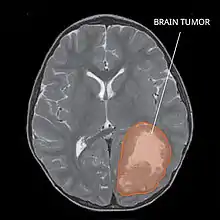

Primitive neuroectodermal tumor of the central nervous system in a 5-year-old

Magnetic resonance image of PNET

Most children that develop primitive neuroectodermal tumors are diagnosed early in life, usually at around 3–6.8 years of age.[2] Symptoms patients present at time of diagnosis include irritable mood, visual difficulties, lethargy, and ataxia.[2] The circumference of the patient's head might also become enlarged and they might be subject to seizures, especially if they have less than one year of life.[2]

Several analysis can be used to determine the presence of the disease. Physical examinations showing papilledema, visual field defects, cranial nerves palsy, dysphasia, and focal neurological deficits are evidences for possible tumor.[2] PNETs can also be spotted through computed tomography (CT) and magnetic resonance imaging (MRI).[2] In images produced by MRIs, an irregular augmentation among a solid mass will indicated the presence of tumor.[3] However, the results of MRIs are usually ambiguous in defining the presence for this specific tumor.[2] In CT scans, the presence of PNETs will be indicated by an elevated density and an increase in volume of the brain.[2] The CT scan can also show calcification,[3] which is present in 41-44% of PNET cases.[2] Since the tumor can be replicated in other parts of the nervous system through the cerebrospinal fluid (CSF), a CSF analysis can also be conducted.[2] A spinal MRI is a fourth type of analysis that is useful in investigating the level of tumor propagation to the spinal cord.[2]